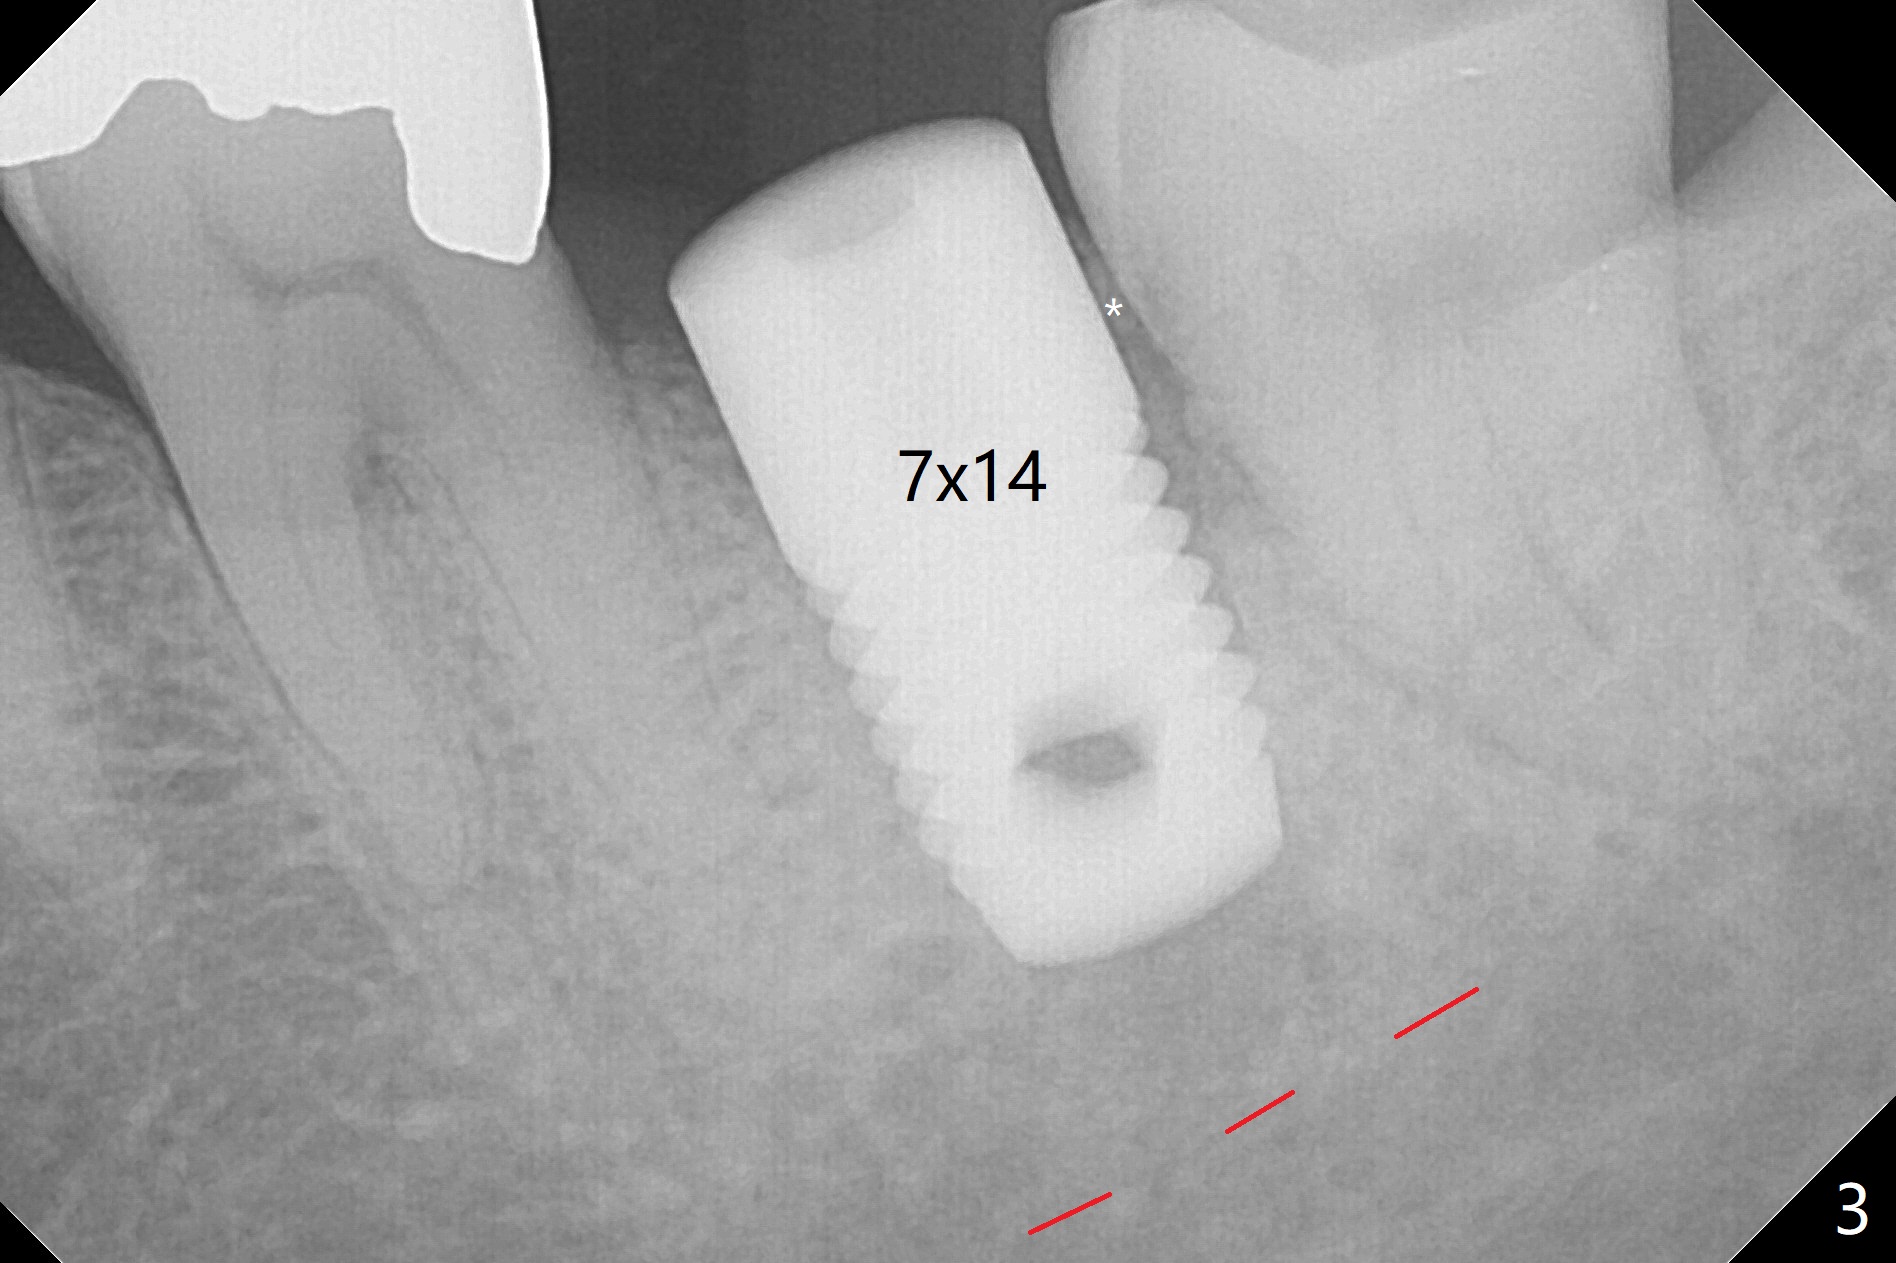

When the mobile tooth #18 with apical granulation tissue is extracted, the socket is large and long (close to the Inferior Alveolar Canal (Fig.2,3 red dashed line). Without drilling, a 7 mm bone level tap does not obtain stability. A 8x17 mm tapered tap reaches the bottom of the socket with minimal stability, but coronally it is close to the tooth #32 (Fig.1). When a 7x14 mm cylindrical tap is placed, it is shy of the bottom of the socket (Fig.2 *), but the trajectory improves. A 7x14 mm tissue-level implant is placed with ~45 Ncm (still not secure) with Vanilla graft placed mainly distolingually (Fig.3). With the large implant, the socket is closed 8 days postop (Fig.4). The soft and hard tissues appear to heal 3 months postop (Fig.5,6). A healing abutment (Fig.7 H) is placed to push the mesial papilla mesially (*). Two weeks later impression is taken with ease because of the healing abutment. There is no bone loss 4.5 months postop (immediately post cementation, Fig.8).